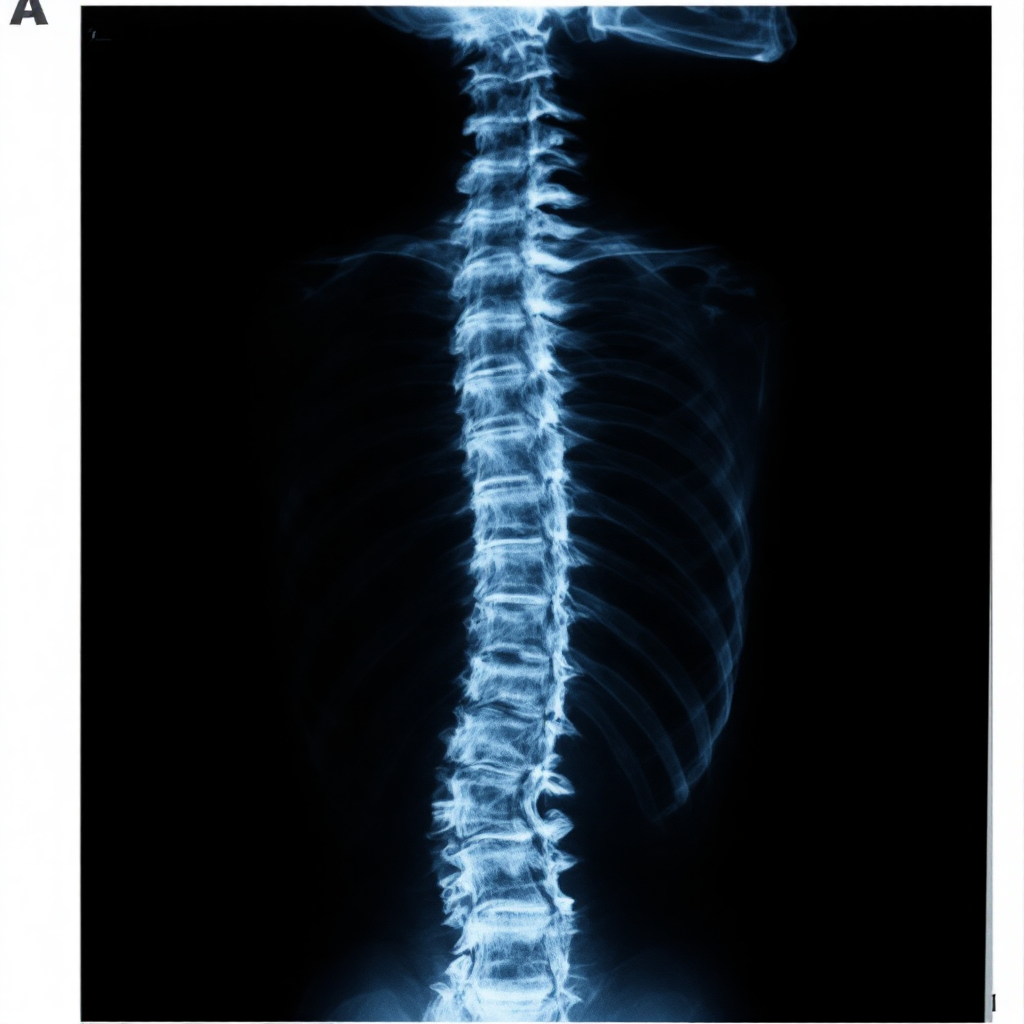

척추 관련 통증이 생기면 단순 엑스레이로는 문제를 명확히 파악하기 어려워요. MRI는 연부 조직과 신경까지 선명하게 확인할 수 있어서, 정확한 원인 진단에 가장 적합한 검사 방식이에요. 특히 디스크 돌출이나 척추관협착증 같은 경우는 MRI 없이는 놓치기 쉬워요.

엑스레이는 뼈의 위치와 배열 정도만 보여주기 때문에, 신경 압박 여부나 디스크 상태를 제대로 판단할 수 없어요. MRI는 신경이 얼마나 눌려 있는지, 어느 위치에서 문제가 발생했는지까지 한눈에 보여주기 때문에 진단 정확도가 훨씬 높죠.